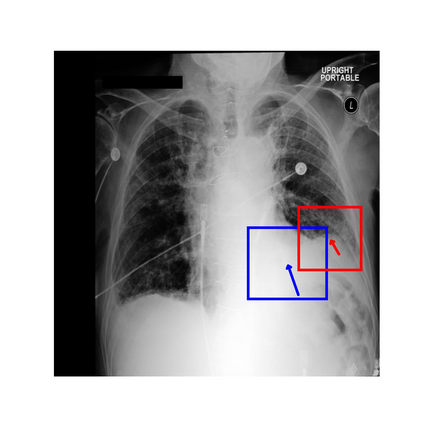

To address these issues, we propose a novel Adaptive patch-word Matching (AdaMatch) model to correlate chest X-ray (CXR) image regions with words in medical reports and apply it to CXR-report generation to provide explainability for the generation process. AdaMatch exploits the fine-grained relation between adaptive patches and words to provide explanations of specific image regions with corresponding words. To capture the abnormal regions of varying sizes and positions, we introduce the Adaptive Patch extraction (AdaPatch) module to acquire the adaptive patches for these regions adaptively. In order to provide explicit explainability for CXR-report generation task, we propose an AdaMatch-based bidirectional large language model for Cyclic CXR-report generation (AdaMatch-Cyclic). It employs the AdaMatch to obtain the keywords for CXR images and `keypatches' for medical reports as hints to guide CXR-report generation. Extensive experiments on two publicly available CXR datasets prove the effectiveness of our method and its superior performance to existing methods.